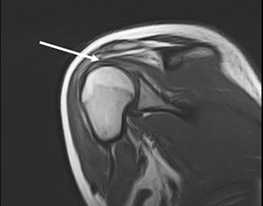

Нами было проведено МРТ обследование, при котором было выявлено повреждение надостной мышцы (указано стрелкой). Пациентке было выполнено оперативное восстановление поврежденной мышцы.